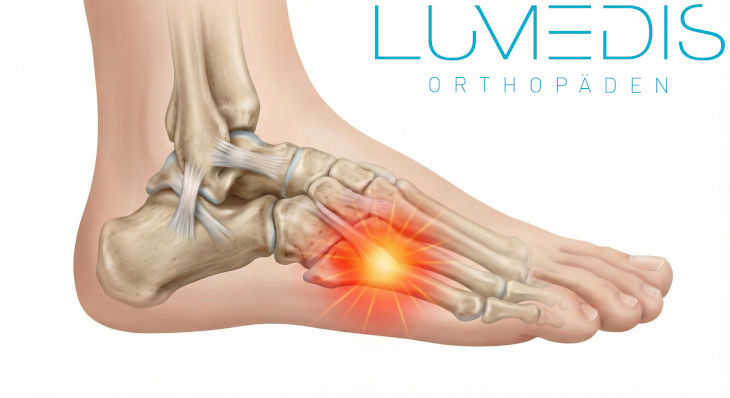

Anatomische Abbildung des Fußes von der Seite.

Rot eingefärbt erkennt man das Fersenbein